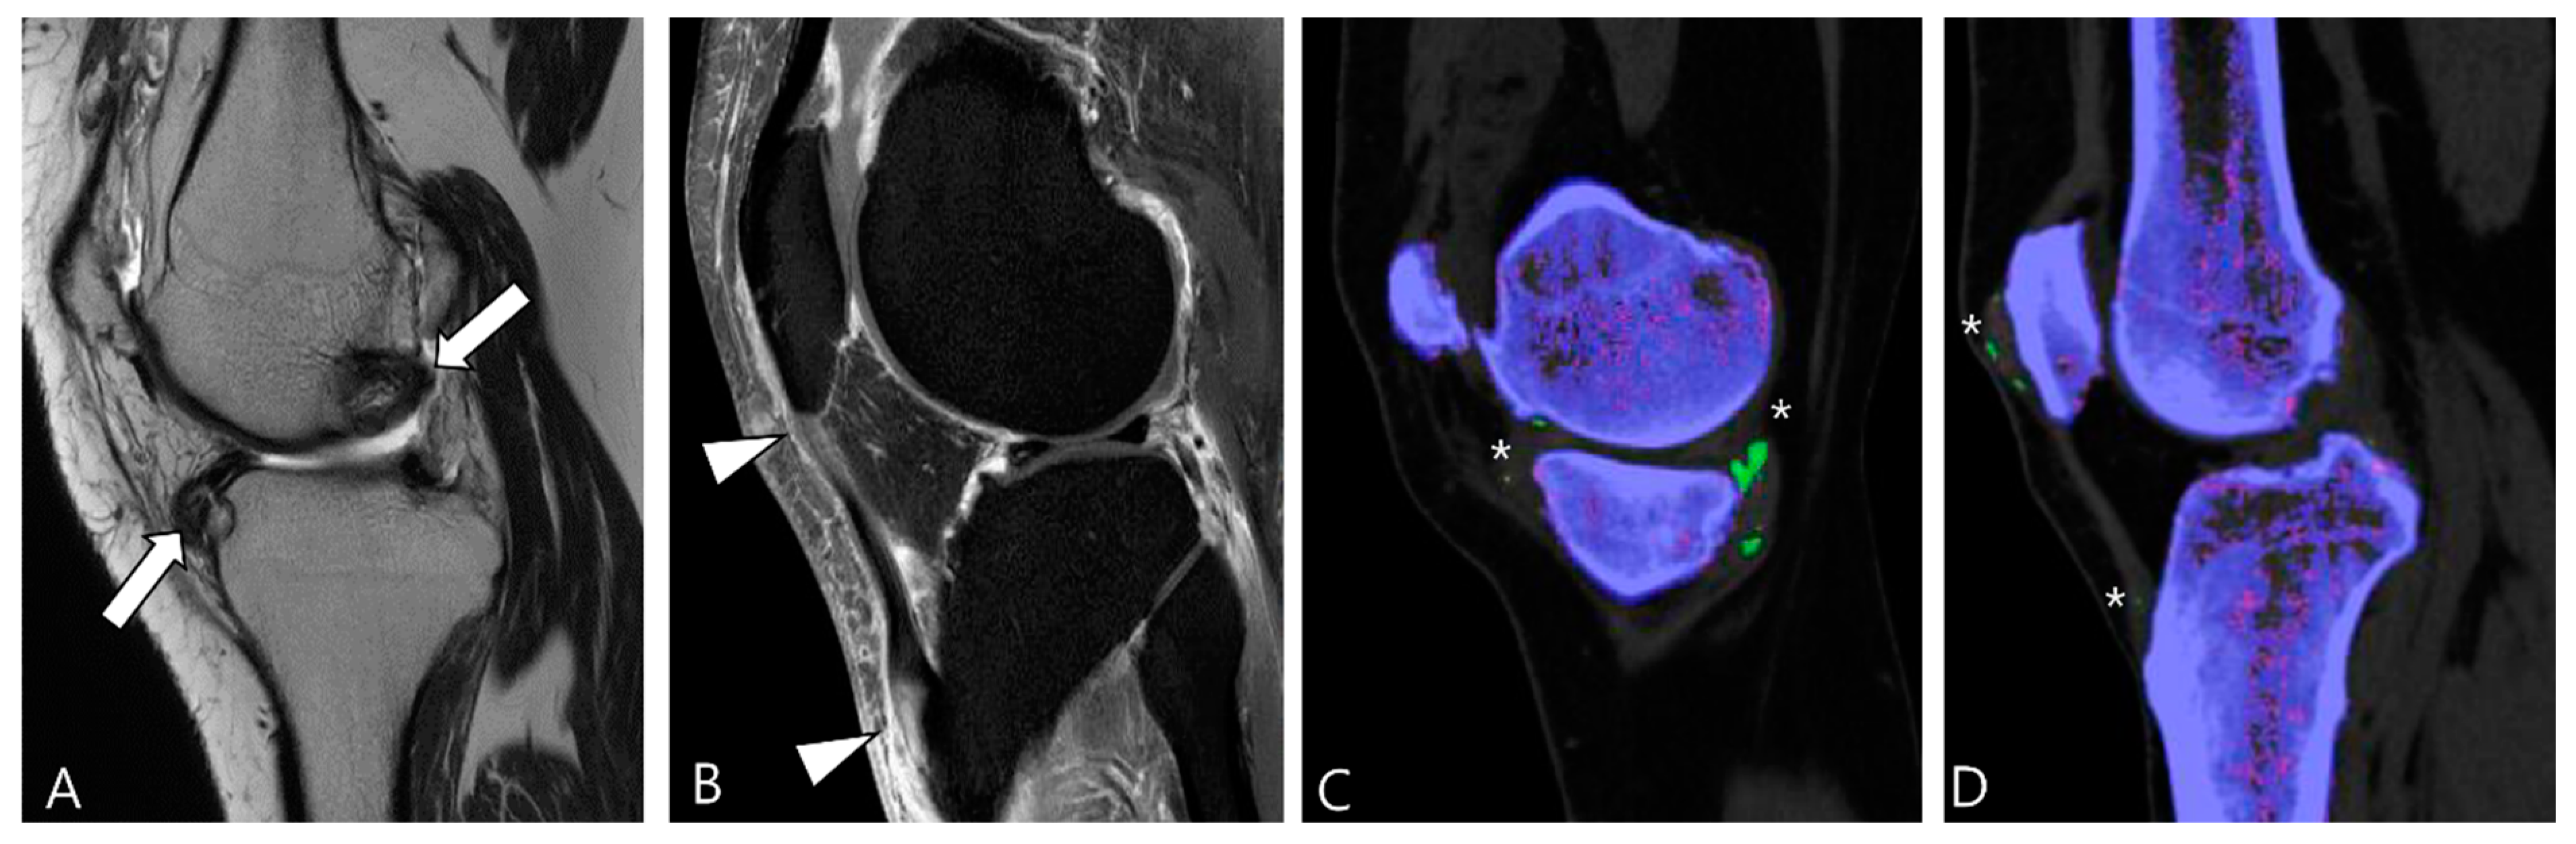

4. MRI Findings for D-TSGCT on Follow-Up MRI

4.1. Treatment Options for D-TSGCT

4.2. Checklists on Follow-Up MRI for D-TSGCT